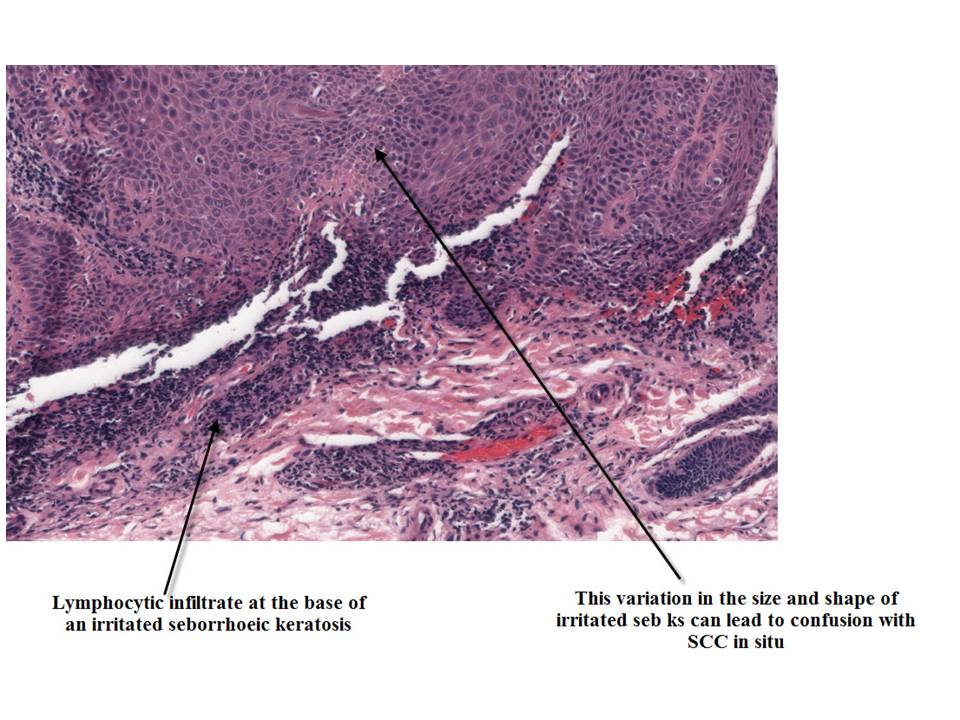

The variants architecturally of Seb ks include acanthotic, hyperkeratotic, clonal and reticulated. These can also be irritated or inflammed. Irritated seb ks show structures called squamous eddies while inflammed show a lymphocytic infiltrate around them. A melanoacanthoma is a deeply pigmented vaiant of a seb k made up of keratinocytes and dendritic melanocytes.

Irritated Seborrhoeic Keratosis